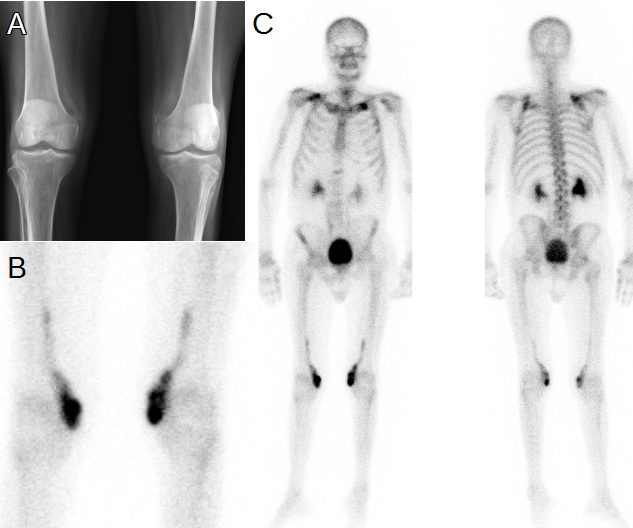

Varón de 56 años con carcinoma de colon intervenido, con evolución tórpida e ingreso en la unidad de cuidados intensivos con encamamiento durante 45 días. Al alta presenta tetraparesia fláccida y dolor intenso en rodillas, con disminución de la movilidad. El laboratorio muestra incremento de la fosfatasa alcalina (AP) y de la tasa de sedimentación eritrocitaria (ESR). En la radiografía simple se observan cambios osteodegenerativos, irregularidades en el borde medial de ambos cóndilos femorales y calcificación de tejidos blandos (fig. 1A). La gammagrafía ósea (GO) con 99mTc-HDP muestra intensa captación del radiotrazador en tejidos blandos de ambas rodillas, siguiendo un trayecto oblicuo ascendente sugestivo de calcificación heterotópica bilateral de músculos sartorios, por lo que se realiza diagnóstico de miositis osificante. Además, presenta intensa captación del trazador en clavícula izquierda y cintura escapular a derecha, de probable etiología osteodegenerativa (fig. 1B y 1C).